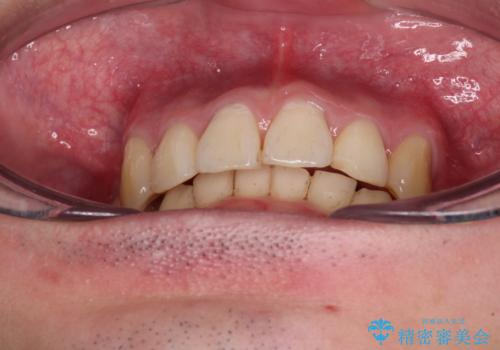

- 八重歯を気にして来院された患者様です。

顕著な上顎の八重歯とディープバイトであったため、上顎の左右第一小臼歯を抜歯することとしました。

犬歯歯根の位置や奥歯の咬み合わせから、ワイヤー装置での治療を強くおすすめいたしましたが、ご本人の強い希望により、妥協的な仕上がりとなることを了解いただき、インビザラインにて矯正治療を行うこととしました。

インビザライン単体で、左右ともに移動の難しい位置に歯根のある犬歯を整えるのは困難と判断し、補助装置を併用することとしました。

ディープバイトや奥歯の咬み合わせなど、インビザライン矯正では限界がありワイヤー装置での治療に及ばない仕上がりとなりました。

ただし、患者様としては八重歯や、それに伴う唇の閉じにくさが改善されたとのことで、納得いく状態での治療終了となりました。